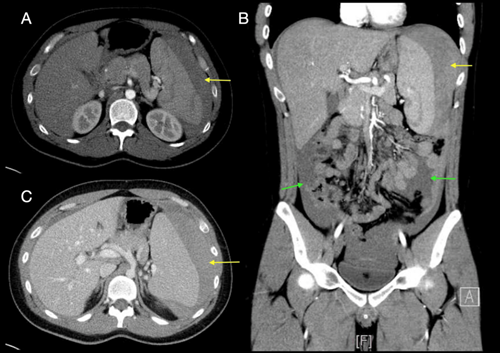

腹部 CT 增强扫描(图1)显示腹腔积血,脾肿大(直径16cm),脾损伤分级为V级(AAST 标准),以脾脏碎裂为特征。

(图1